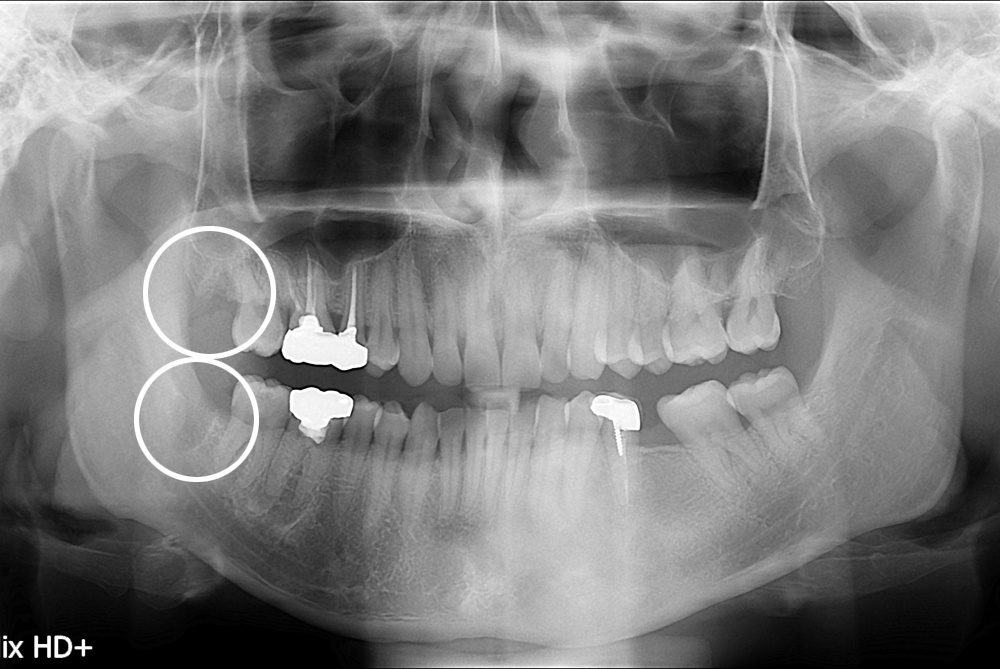

[사랑니] 난발치 사랑니 발치

치료전 : 2017-10-04